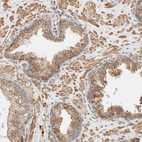

Immunohistochemical staining of human testis shows strong positivity in nuclear membrane in spermatogonia in cells in seminiferous ducts in addition to moderate cytoplasmic positivity.